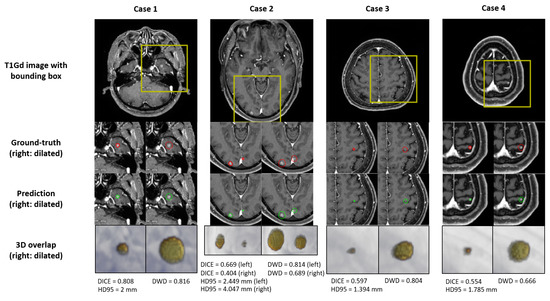

The DL performance for test-set BM segmentation is summarized in Table 3. The Dice coefficient showed a value of 55% for all BM. Our test-set consisted of small-volume BM, mostly <0.1 cc, and even a slight deviation from the prediction showed a large difference in the DICE. To compensate for this, DWD and HD95 were used as the segmentation performance metric. In the BM with a volume <0.04 cc, DWD and HD95 showed values of 63.2% and 1.689 mm except for those that were undetected, respectively, and the BM with a volume >0.04 cc showed values of 78.6% and 2.158 mm, respectively. For all BM, the DWD value was 75% and the HD95 value was 2.057 mm. Some examples of segmentation are shown in Figure 5.

Figure 5. Examples of the ground-truth delineation and predicted delineation. The yellow bounding box in the first row indicates the area where false positives occurred. The second row shows the manual delineation of the tumor volume and the manual delineation dilated to 3 mm. The third row shows the predicted delineation from DL and the predicted delineation dilated to 3 mm. For the second and the third rows, red and green indicate manual and predicted delineation, respectively. The last row shows the 3D rendering overlapped with manual delineation and predicted delineation, and 3D rendering dilated to 3 mm each. In the last row, renderingRendering in red is predicted delineation and rendering in yellow is manual delineation.